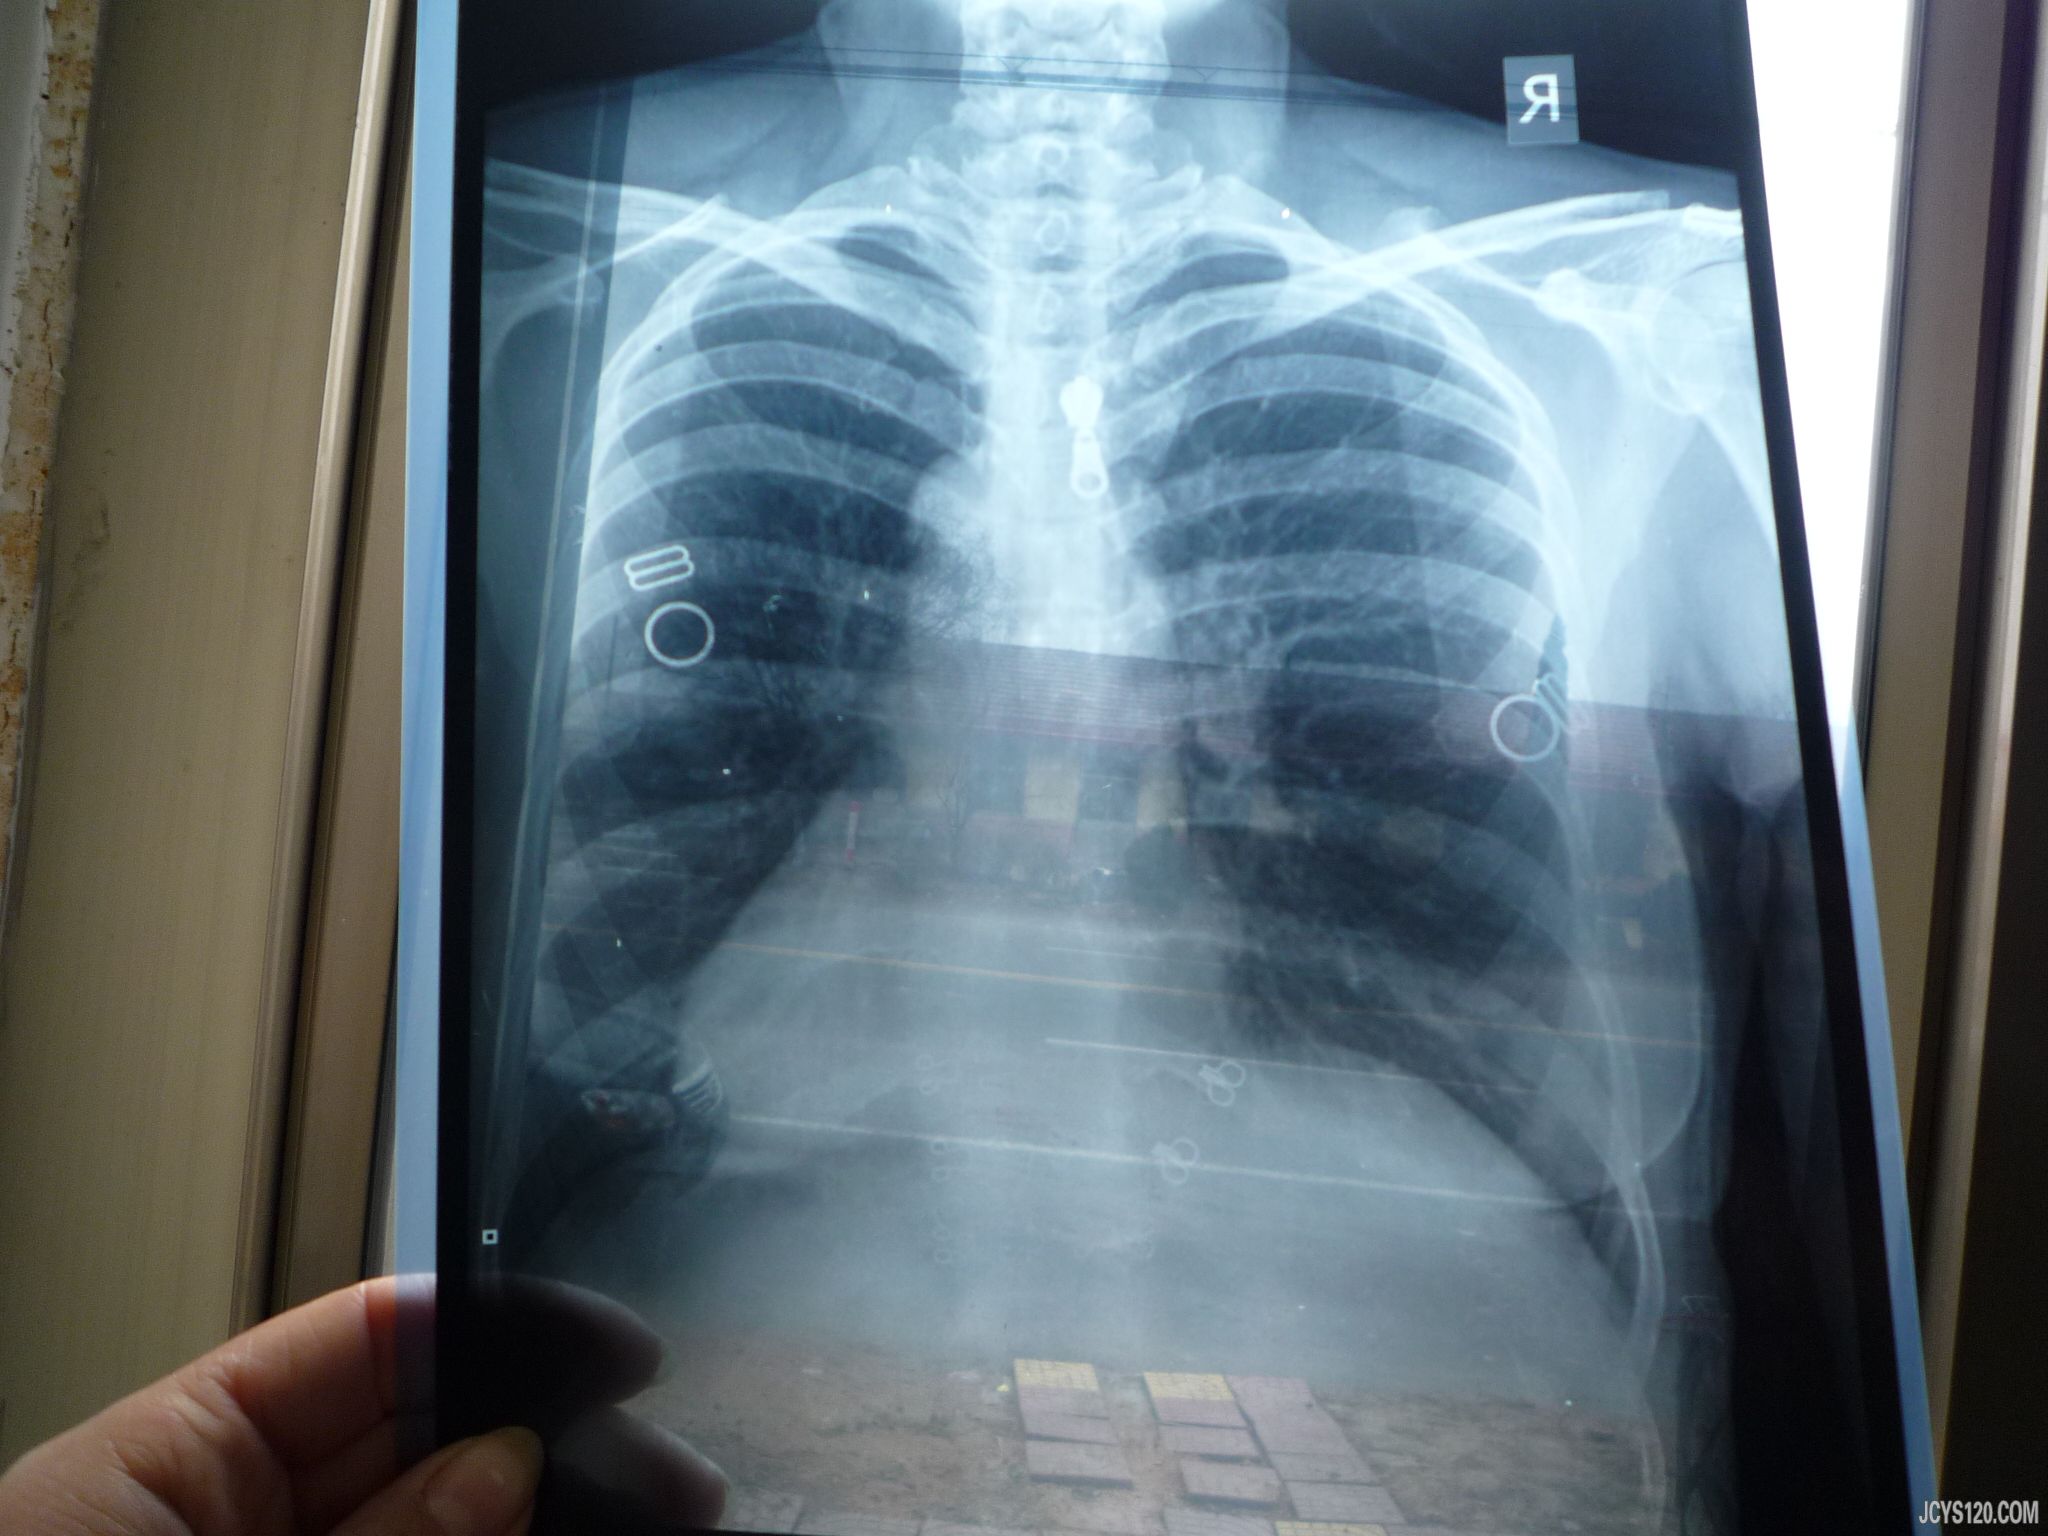

病史:患者于4天前开始发烧咳嗽,最高体温39度, 全身无力,口苦口干,鼻塞鼻涕,咽喉不适。在我诊所输液治疗:5%GS 250 克林霉素 1.2 NS250 病毒唑 0.5 地塞米松5毫克。( 口服维c银翘片 甘草片消炎止咳片 发烧时口服瑞芝清)输液3天体温正常。但是咳嗽有痰,(地塞米松第二天减量 2毫克 )但是病人不放心想去医院检查今天到乡镇医院检查,医院大夫查血分析,尿常规,支气管肺正侧位片 检查完后说你的病情很重 肾脏不好 赶快去大医院进一步检查很危险,听后患者几乎吓瘫,(都想到要卖房子)不知所措,患者既往身体健康,就是这次感冒有点不适,现在体温正常,咳嗽不是很重,有痰口干口苦,听诊有痰鸣音,余(--) 查体 体温37.3 咽喉正常 扁桃体 不大双肺呼吸音粗 有痰鸣音 心脏听诊(—)眼睑不肿胀 四肢不肿胀,血压正常。体温过一会又量37度 。 下面我上传该患者检查结果 大家看一下 是否像乡镇医院所说如此危险 真的需要赶快去医院进一步复查呢?

肺纹理增粗,白细胞不高,中粒比例不高。可以停了激素,输阿奇,阿奇不在肾脏代谢。尿蛋白是不是与感冒有关?是不是在月经期?可以观察几天,咳嗽好了再复查。因为病人血压不高,没有水肿,情况不是很急。 以上纯为个人观点。

浮生 发表于 2013-2-1 15:21 static/image/common/back.gif 肺纹理增粗,白细胞不高,中粒比例不高。可以停了激素,输阿奇,阿奇不在肾脏代谢。尿蛋白是不是与感冒有关 ... X光片目前仅支持支气管炎诊断,血常规也仅仅支持贫血,但是患者长期高热不退,还是难以排除肾脏疾病,不过我偏向于肾盂肾炎。